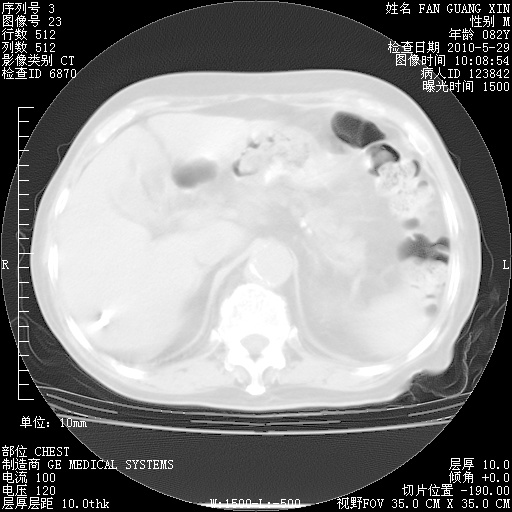

再治疗10天后的肺部CT

再治疗10天后的肺部CT 纵膈窗

从白细胞总数和中性比例看好像合并感染。肺部纹理好像比上次多,支气管炎?其他感染?

阅读此次胸部CT,肺间质渗出性改变较入院时有吸收。目前从体温、白细胞、中性分叶明显增高,肯定存在细菌感染(发生医院感染哦,若无消化道及泌尿系统等感染的依据,肺部感染可能大)。若你院头孢哌酮舒巴坦钠耐药率较高,同意你的方案,若48小时体温仍高,可考虑使用碳青霉稀类抗菌药物,同时可予超声雾化、注意滴数时加大液体量。白蛋白33.30g/L较低哦,需加强营养等支持治疗。